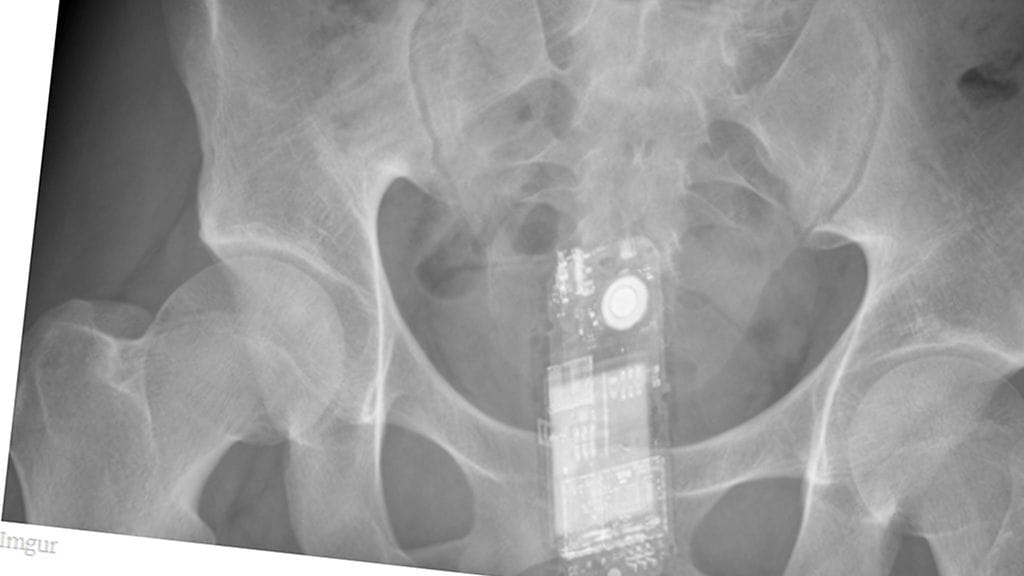

Erikoiset röntgenkuvat saavat ihmettelemään vain yhtä asiaa: voivatko ihmiset oikeasti olla näin typeriä?

Mikä menee sisään, ei välttämättä tule ulos ihan itsestään. Unilad-sivuston julkaisemat röntgen-kuvat asioista, joita himokkaat miehet ovat sisäänsä tunkeneet, eivät ensituntumalta vaikuta edes mahdollisilta.